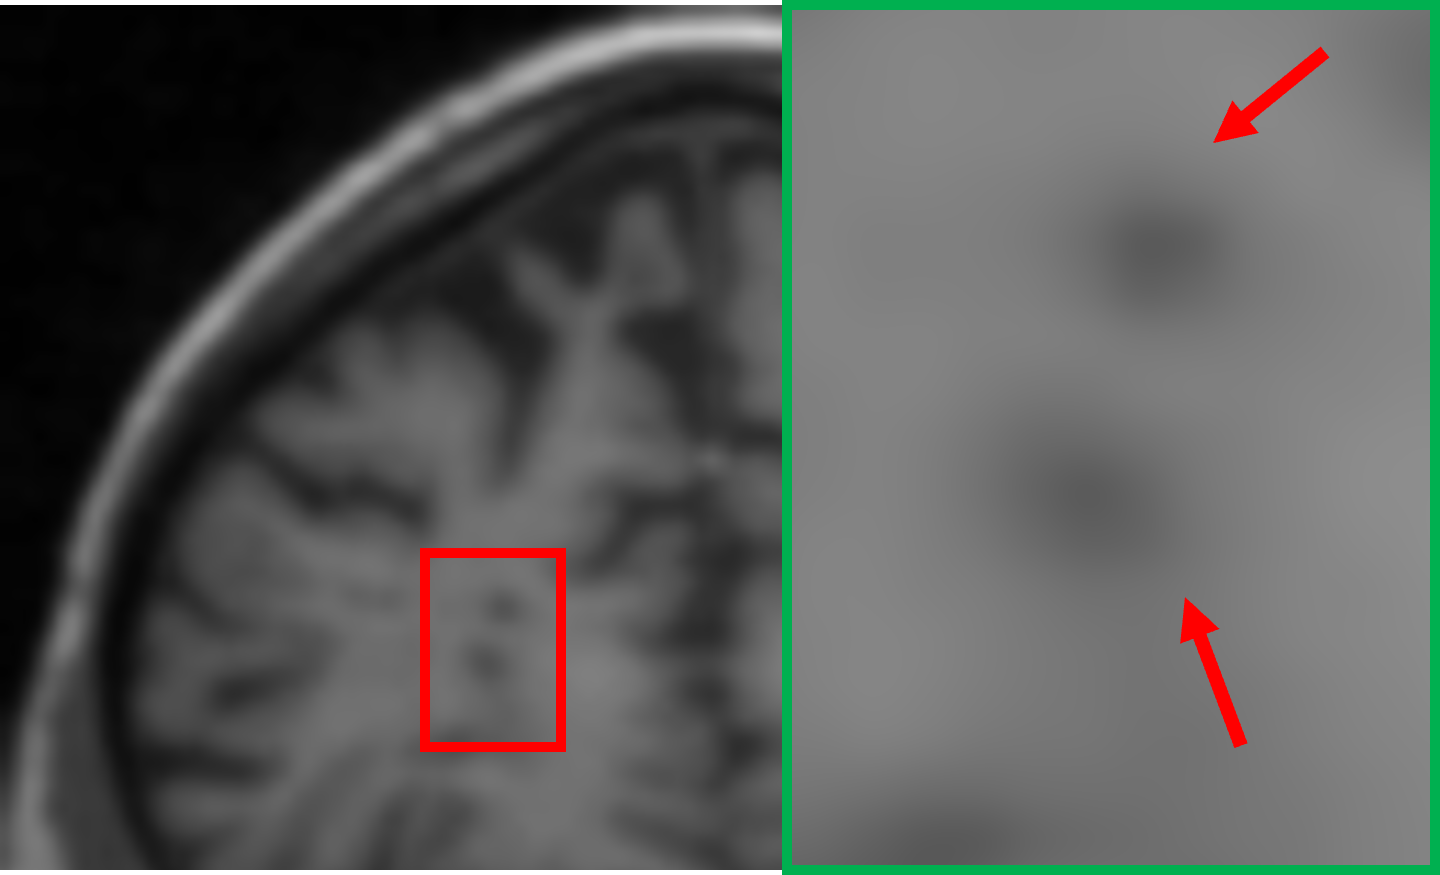

IV-D Deployable flexibility analysis of the student model

Beyond its lightweight architecture, the student model demonstrates a remarkable deployable ability to perform SR tasks across MRIs of varying resolutions without requiring additional training. This stems from its training process that involves exposing the student model to inputs and targets across a range of resolutions, equipping it with the ability to handle diverse resolution scales. For this, we explore two common SR scenarios: 1.5T to 3T and 3T to 7T MRI. We include the recently proposed Implicit Diffusion Model (IDM) [35], a novel method for continuous image SR, as a benchmark in our evaluation. In our study, the voxel sizes of the MRI scans are 2mm×\times×2mm×\times×2mm for 1.5T, 1.5mm×\times×1.5mm×\times×1.5mm for 3T, and 0.7mm×\times×0.7mm×\times×0.7mm for 7T. Since the focus is on 2D slice-based SR, we configure both the magnification factors for IDM and the step allocations for our proposed student model to match the required SR ratios. Specifically, for the 1.5T to 3T scenario, a magnification factor of 1.8 is employed for IDM, corresponding to an allocation of 4 steps out of the total 20 steps for the student model. Similarly, for the 3T to 7T scenario, a magnification factor of 4.6 is applied for IDM, corresponding to an allocation of the remaining 16 steps for the student model.

As illustrated in Figure V, for the 1.5T-to-3T task, the teacher model is not applicable as it is designed to directly perform SR from 1.5T to 7T. The output of IDM in this scenario shows significant blurring, particularly in the cerebellum region, with minimal perceptible improvement over the input, indicating a limitation in capturing the finer structures. In contrast, our student model achieves results that closely resemble the 3T ground truth, effectively recovering structural details and textures. For the 3T-to-7T task, the teacher model, when directly applied to 3T data, generates overly sharpened outputs, reflecting its sensitivity to input-specific constraints and its lack of adaptability to intermediate resolutions. However, the student model consistently outperforms IDM in this scenario as well, delivering results with better alignment to the 7T ground truth and more balanced enhancement of fine details. These observations highlight the flexibility and robustness of the student model across varying resolution scales, emphasizing its superiority in deployable SR scenarios.